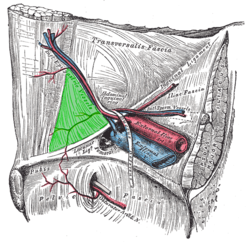

Onde está o anel inguinal interno?

Na fáscia transversalis

Quais são as estruturas inguinais importantes que estão na fáscia transversalis?

Quem compõe a parede posterior do canal inguinal?

Que estrutura compõe a parede anterior do canal inguinal?

Aponeurose do músculo oblíquo externo